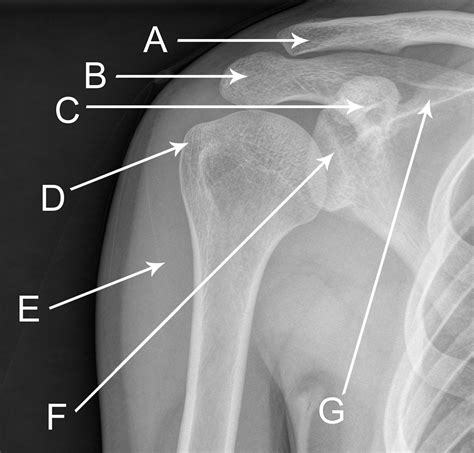

Understanding the significance of a shoulder X-ray normal result is crucial for both medical professionals and patients. A shoulder X-ray is a common diagnostic tool used to evaluate the bones, joints, and surrounding soft tissues of the shoulder. This imaging technique helps identify fractures, dislocations, arthritis, and other abnormalities. However, interpreting a shoulder X-ray normal result requires a thorough understanding of the anatomy and potential pathologies that can affect the shoulder.

The shoulder is a complex joint composed of several bones, muscles, and ligaments. The primary bones involved are the humerus (upper arm bone), scapula (shoulder blade), and clavicle (collarbone). The shoulder joint is a ball-and-socket joint, allowing for a wide range of motion. The rotator cuff, a group of muscles and tendons, plays a crucial role in stabilizing the shoulder and enabling movement.

A shoulder X-ray is a non-invasive imaging test that uses electromagnetic radiation to produce images of the shoulder joint and surrounding structures. This test is often the first step in diagnosing shoulder pain or injury. The X-ray can reveal fractures, dislocations, arthritis, and other bone abnormalities. However, it may not always show soft tissue injuries, such as tears in the rotator cuff or ligaments.

When a shoulder X-ray normal result is reported, it means that the X-ray images do not show any visible abnormalities in the bones or joints. This can be reassuring for patients experiencing shoulder pain, as it indicates that there are no obvious fractures or dislocations. However, it is important to note that a normal X-ray does not rule out all possible causes of shoulder pain.